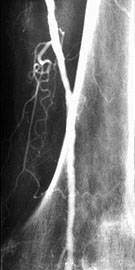

腹部和胸部很多实质脏器的血管造影诊断,跟四肢和脑血管评估一样,被认为是格外有价值的,因为其辅助了术前诊断。然而一些血管造影的先驱感到沮丧,是因为他们如此地接近病变而不能进行治疗。介入放射学历史性的突破发生在1964年。完全闭塞的髂动脉再通巧合的在出现诊断影像学形成之前,即进行血管造影的时候,导管有时会偶然通过闭塞的动脉段,这激发了Charles Dotter产生经皮腔内血管成形术(PTA)的想法。并由此诞生了一场医学领域内的革命。 介入放射学之父:Charles T. Dotter (1920-1985) ![]()

Dotter 出生于马萨诸塞州的波士顿市。在纽约医院接受放射学培训后,他进入了康奈尔医学院。最终成为在波特兰(美国俄勒冈西北部港市)俄勒冈州立大学的血管放射学家,。1952年,32岁时他成为Oregon医学院教授和放射科主任。他首先改变了Seldinger技术,使之用于治疗的目的。1964年1月他使用创新的扩张导管在一个84岁妇女身上进行了股浅动脉一个短的闭塞节段的成功血管再通。经皮腔内血管成形术由此创立,一场医学领域里的革命就这样静静悄悄地开始了[1]。

这种最后被称为“经腔血管成形术 (transluminal angioplasty)”技术是通过在股动脉使用多个不断增加直径的导管扩张动脉阻塞病变以改善病人下肢动脉的血流。这项在现代介入医生看来非常“老土”技术,却是具有里程碑意义的事件。因为它从此开创了血管介入性放射学的发展历程。